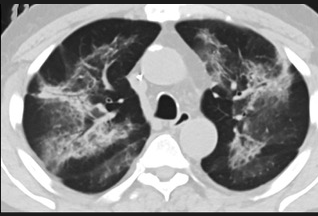

更值得注意的是,有之前应对过武汉新冠疫情的中国权威肺病专家,在查阅了60篇涉及美国“电子烟肺病”病例的研究论文,并对其中142位电子烟肺病患者的250张肺部影像图片、临床信息以及文献原文进行了仔细全面的研究后,发现这些病例中有16个更有可能是新冠肺炎的“疑诊患者”,有5个临床症状和治疗情况相对完整的患者,还被这些专家认定为了“中度可疑”。另外,这16个病例中有12个病例的发病时间,都在2020年以前。

(这4张图,是专家怀疑被误诊为电子烟肺病的其中一个病例的肺片。专家表示,他们不是仅仅通过一张影片做判断的,而是通过这4张涵盖了这名病例肺部多天变化情况的影片进行的研判,认为该病例的病程进展跟新冠更为相似)

所以,会不会在2019年所谓的“电子烟肺病”爆发的同时,美国就已经出现了新冠肺炎或当时还是“不明原因的肺炎”,但被误诊了呢?这个可能性,在无法看到调取美国全部电子肺病原始病例的情况下,是无法被排除的。